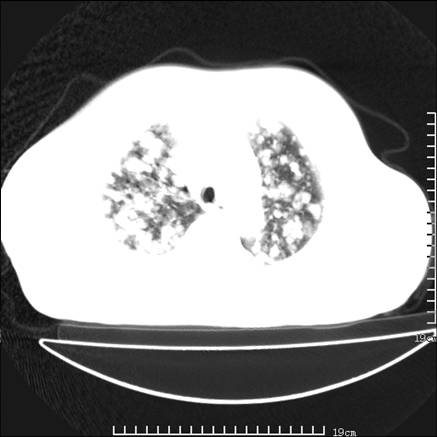

张男,75岁,干咳半年余,小便不利二年,b超检查前列腺增大,未见明显肿块;前列腺癌血生化检查多项指标明显增高。

双肺内多发转移瘤,纵膈淋巴结转移。来源前列腺?建议盆腔mri进一步检查。

双肺转移满了。

两肺广泛转移瘤。